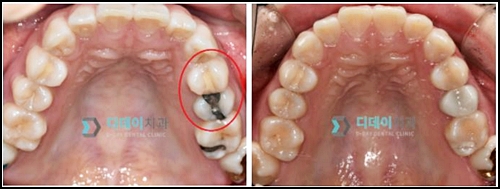

이전에 시술했던 아말감이 오래되고, 충치가 추가로 발생하였기 때문에 본원에 방문해 주신 환자분의 사례입니다.

치료 전/후 (2021 - 05 - 18)

오래된 아말감은 2차 충치 우려가 있기 때문에 검진 후 교체가 필요한데요.

우선 아말감과 충치를 완전히 제거한 후, 치아를 때우는 방식의 레진 치료를 도와드렸습니다.

레진은 치아 색과 유사하면서 비용도 저렴하고, 당일 치료가 가능하다는 점에서 메리트가 있습니다. :)